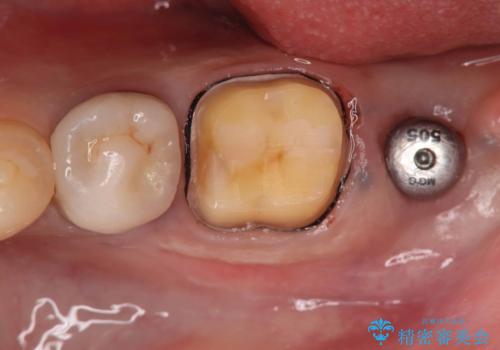

- 過去にヘミセクションが行われていたと思われる左下7番は、大きな歯根嚢胞および根尖病変が認められ、さらに骨縁下カリエスを伴っており、歯肉には瘻孔が形成されている状態でした。

保存は困難と判断し、左下7番は抜歯即時インプラントによる治療を行いました。

抜歯と同時にインプラントを埋入するため、歯茎を切開する必要がなく、術後の痛みが出にくい治療方法です。

手術は1回で完了し、被せ物を装着するまでの治療期間も約3か月と、身体的・時間的な負担を抑えることができます。

今回の患者様も、治療直後に痛み止めを1錠服用されたのみで、その後は痛みが出ることなく、追加の服用は不要だったとのことでした。